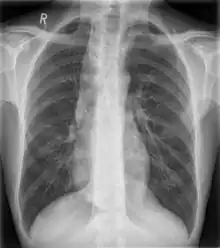

| Widened mediastinum | |

|---|---|

| Other names | Mediastinal widening |

![]() | |

| Widened mediastinum in a patient with achalasia | |

Widened mediastinum/mediastinal widening is where the mediastinum has a width greater than 6 cm on an upright PA chest X-ray or 8 cm on supine AP chest film.[11]

A widened mediastinum can be indicative of several pathologies:[12][13]